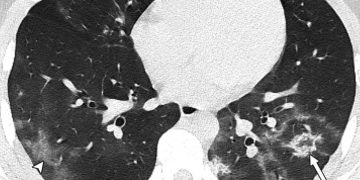

«Μία εικόνα χίλιες λέξεις. Αξονικές τομογραφίες νέων κάτω από 18 έτη με Covid-19 (18 ετών, 15 ετών, 14 ετών και 8 ετών). Κανένας ασθενής δεν είχε υποκείμενα νοσήματα ή ανοσοκαταστολή. Οι ασθενείς δεν χρειάστηκαν συμπληρωματικό οξυγόνο, διασωλήνωση ή ΜΕΘ. Πρόκειται για απλά-κοινά περιστατικά Covid-19. Ωστόσο έχουν πολύ “εντυπωσιακές” βλάβες και είναι άγνωστο τι θα προκαλέσουν αυτές οι βλάβες σε βάθος χρόνου. Για την πλειονότητα του κόσμου το ερώτημα είναι απλό: Θέλουν να υποβάλουν τους πνεύμονές τους σε αυτές τις βλάβες για να δουν αν αντέχουν; Και αν αντέξουν την πρόκληση (όπως προβλέπεται ότι θα αντέξουν οι περισσότεροι νέοι) θέλουν να δουν πόσα χρόνια ή αντοχές έχασαν στην πορεία; Με το εμβόλιο προστατεύουμε τους πνεύμονές μας από βαρύτατη καταπόνηση!»